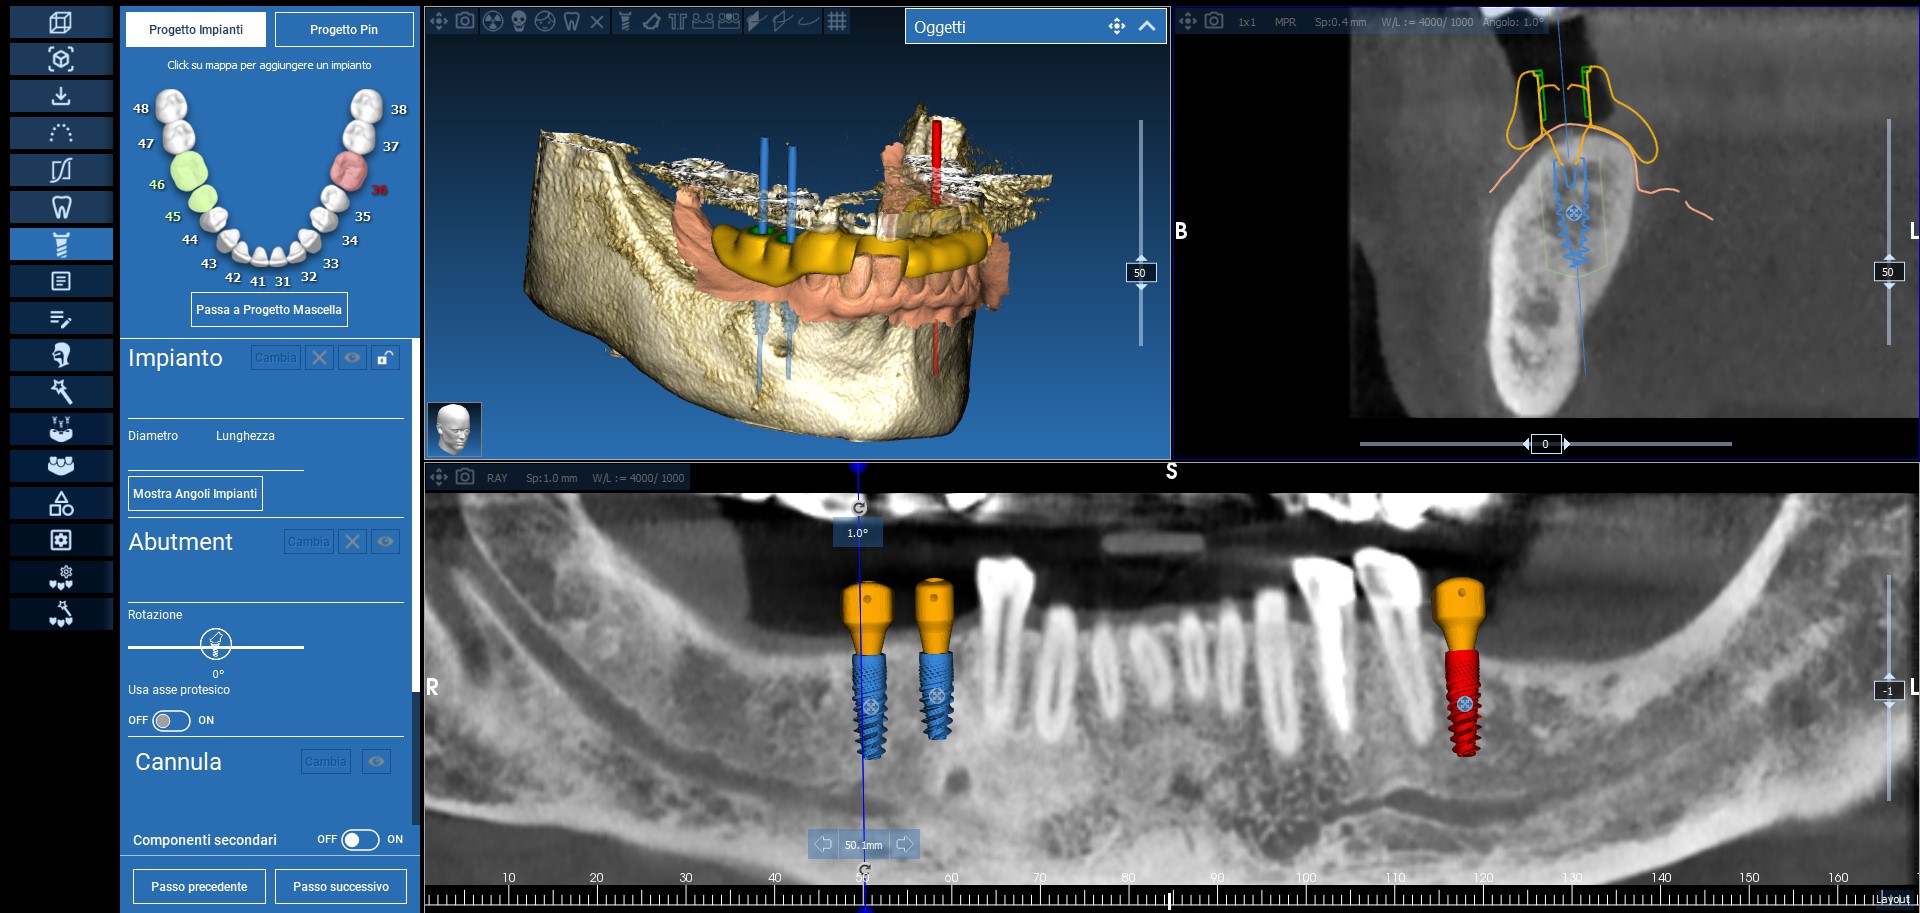

Già in prima visita si procedeva alla rilevazione di una scansione intraorale con scanner TRIOS 3 (3SHAPE, Copenhagen, Danimarca) e all’esecuzione di una CBCT (NewTom, Cefla, Bologna, Italia) per la raccolta di tutti i dati utili alla realizzazione di una progettazione computer assistita. I dati DICOM e i file Stl venivano dunque importati in un software di pianificazione digitale (REALGUIDE Software Suite, 3DIEMME, Cantù, Italia). Il software permetteva come prima cosa l’identificazione del nervo alveolare inferiore, sia di destra che di sinistra, garantendo la pianificazione dell’intervento in massima sicurezza.

Successivamente, dopo l’esecuzione di una ceratura diagnostica digitale, veniva identificata la posizione corretta dove inserire i tre impianti. A questo punto veniva stabilito quale tipo di iPhysio® utilizzare per ogni singolo impianto: queste particolari viti di guarigione, infatti, possono essere scelte in base alla tipologia dell’elemento da sostituire, e allo spessore del tragitto transmucoso, offrendo i vantaggi sia degli abutment customizzati che di quelli commerciali (Figura 3).

Fig. 3. Ceratura e progetto digitale di posizionamento implantare e delle viti di guarigione.

Ultimati questi passaggi, si passava alla progettazione di una dima chirurgica a supporto dentale realizzata con tecnologia Polyjet (Stratasys, Rehovot, Israele), in modo da trasferire chirurgicamente in maniera pianificata e guidata, dal virtuale al reale, la pianificazione realizzata sulla piattaforma software (Figure 4, 5, 6, 7).

Fig. 4. Pianificazione della dima chirurgica a supporto dentale.